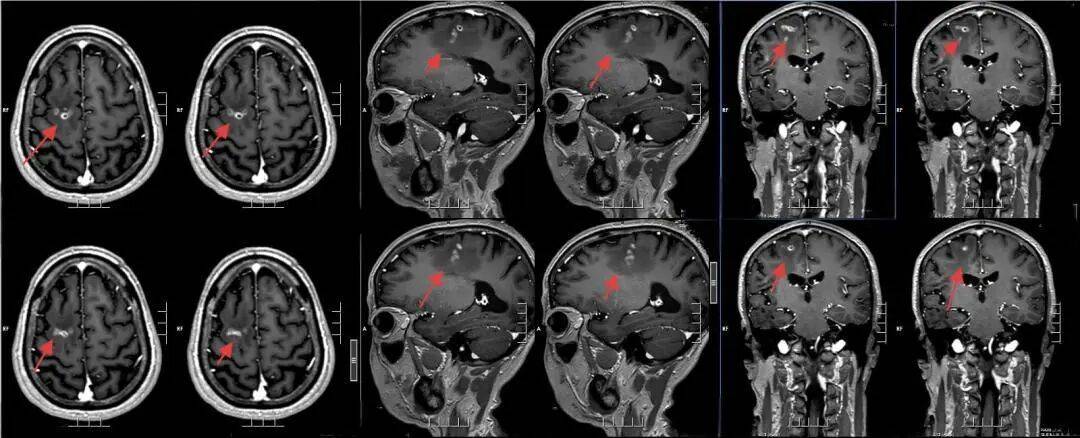

该院神经外二科张旭标副主任医师接诊后,根据影像结果,发现其右额叶病变,局部肉芽肿形成伴周围组织水肿怎么申请皇冠信用网 。“这是大脑为了隔离‘入侵者’筑起一道‘隔离墙’,周围的脑组织被刺激得肿胀。”张旭标解释,这些影像特征高度指向脑裂头蚴病。经比对,病灶范围稳定,手术时机成熟。

术前影像

手术采用神经导航技术,精确定位病变,张旭标在显微镜下小心抓取寄生虫、清理“虫窝”,避免损伤周围功能区脑组织怎么申请皇冠信用网 。术中,一条长约10厘米的灰白色寄生虫被完整取出。术后病理报告证实为裂头蚴。